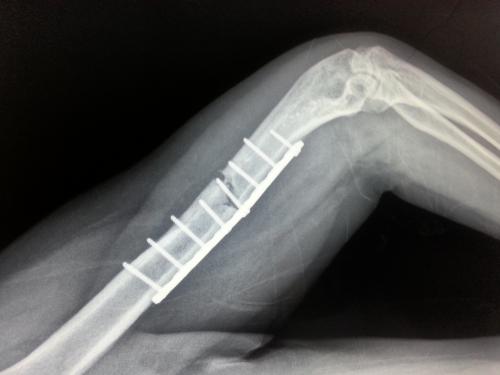

主要形式:加强患肢关节的主动运动,使各关节迅速恢复正常活动。下肢骨折病人可作上下坡、上下楼活动,在拐杖或手杖保护下,作一些负重的活动。骨折程度有轻重之分,重者多需要手术处理。但术后有些病患会出现肢体肿胀,十分难受。

骨折术后常有肢体肿胀出现,这主要是骨折所引起的局部血液循环不畅,在术后早期尤为多见。肿胀时间因人而异,年轻病患静脉瓣重建速度以及患处恢复时间均较老年病患的快,因而肿胀时间可能相对持续较晚。病患的卧床时间也会影响到消肿速度。卧床时间越长,肿胀持续越久,因为长期卧床会导致深静脉瓣的退化,进而导致血运受阻,引发肿胀。